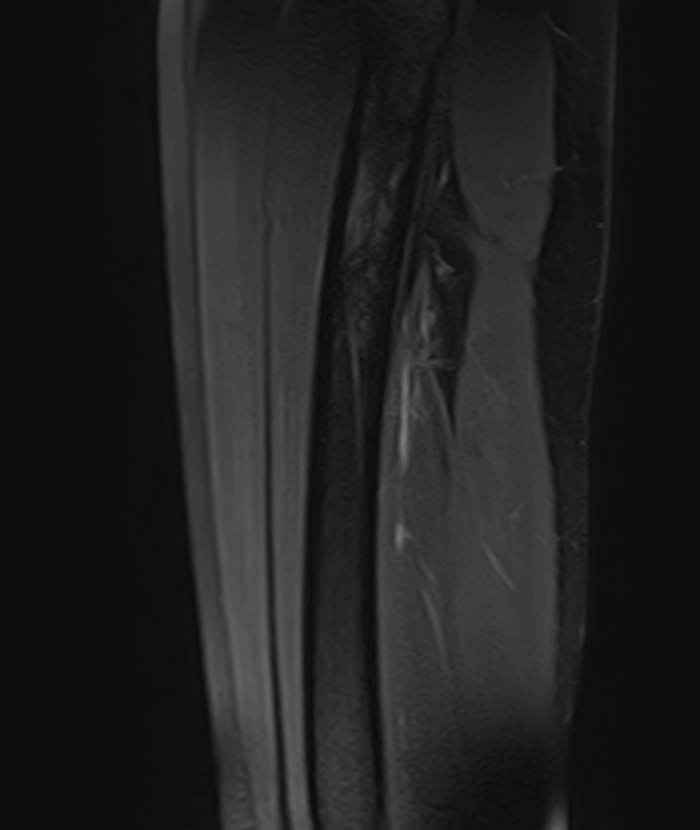

Магнитно-резонансная томография мягких тканей широко используется для детальной визуализации мягкотканных структур.

С помощью МРТ можно оценить состояние мышц, фасций, межфасциальных пространств, синовиальных оболочек, связок, сухожилий, сосудисто-нервных пучков, лимфоузлов и лимфатических протоков, надкостницы, кожи, подкожно-жировой клетчатки.

Метод магнитно-резонансной томографии по сравнению с другими исследованиями дает наиболее полную информацию о состоянии мягкотканных структур (по сравнению с УЗИ, традиционным рентгеновским исследованием и КТ). Кроме того, для повышения диагностической визуализации, например, при подозрении на развитие опухолевых процессов, дополнительно применяется контрастное усиление путем внутривенного введения гадолиниевого контрастного препарата.

- Травматические повреждения мягких тканей (разрывы сухожилий, растяжения связок, повреждения мышц).